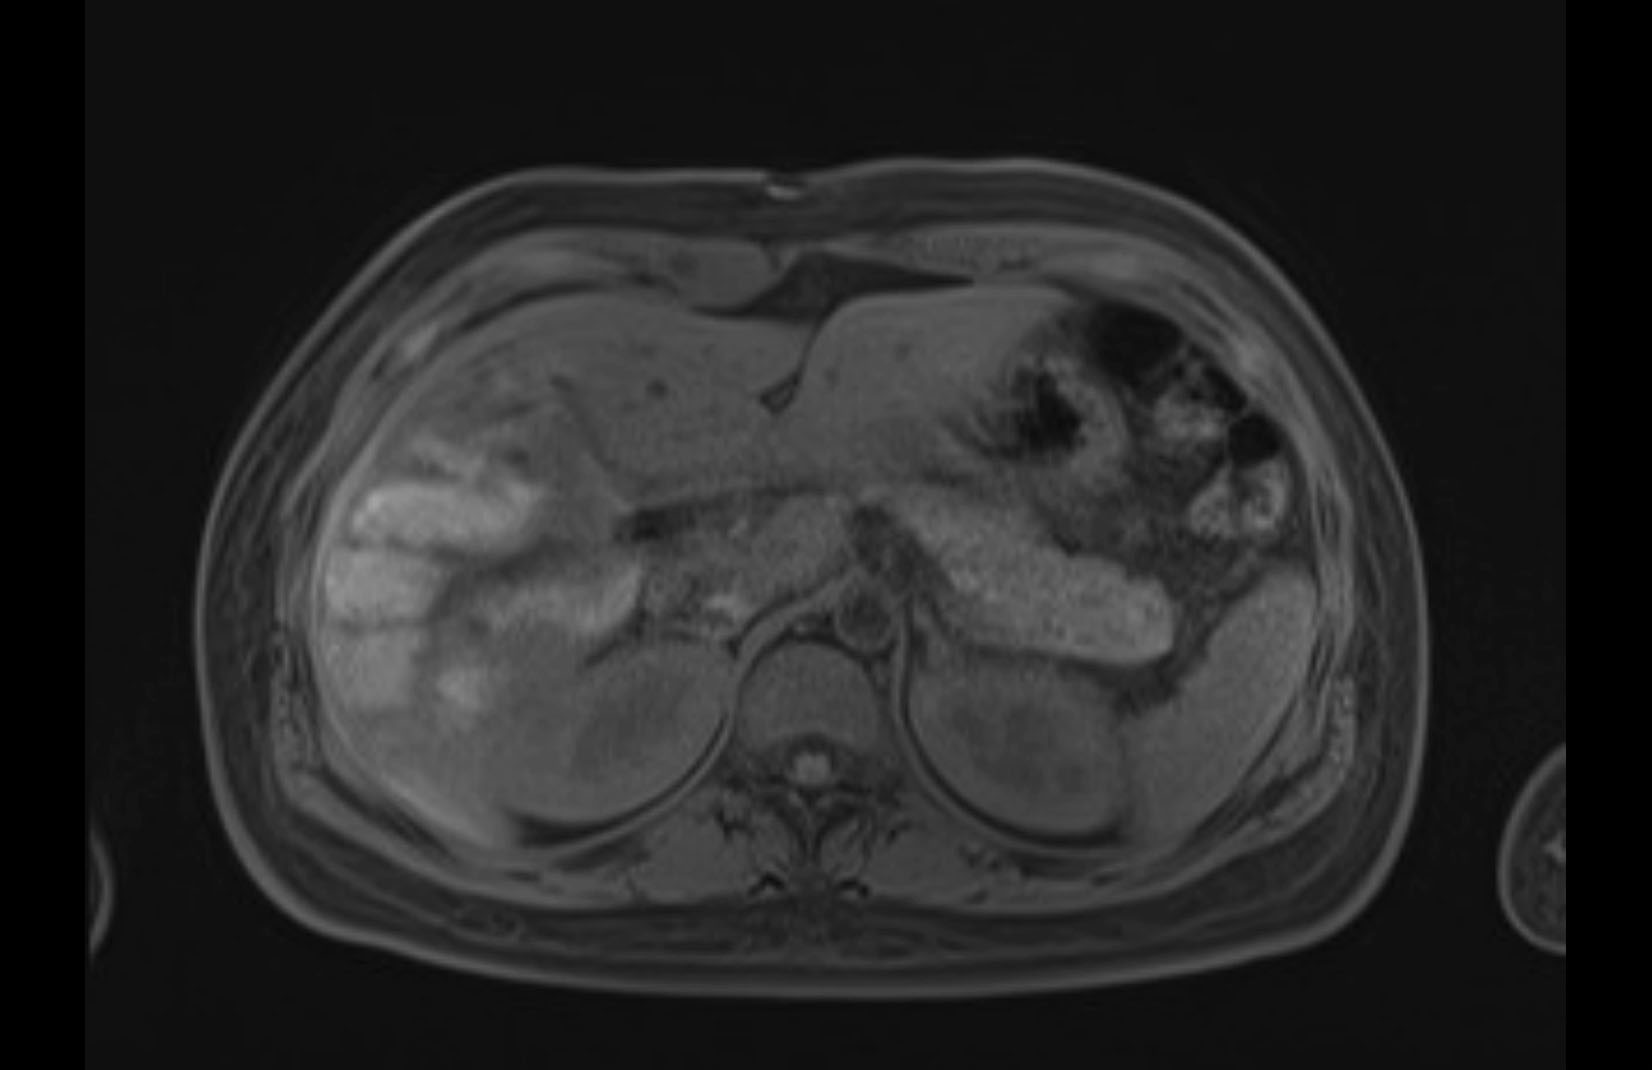

MRI T1

MRI T2

Imaging analysis

Based on initial findings, which issue(s) would you be most concerned about?